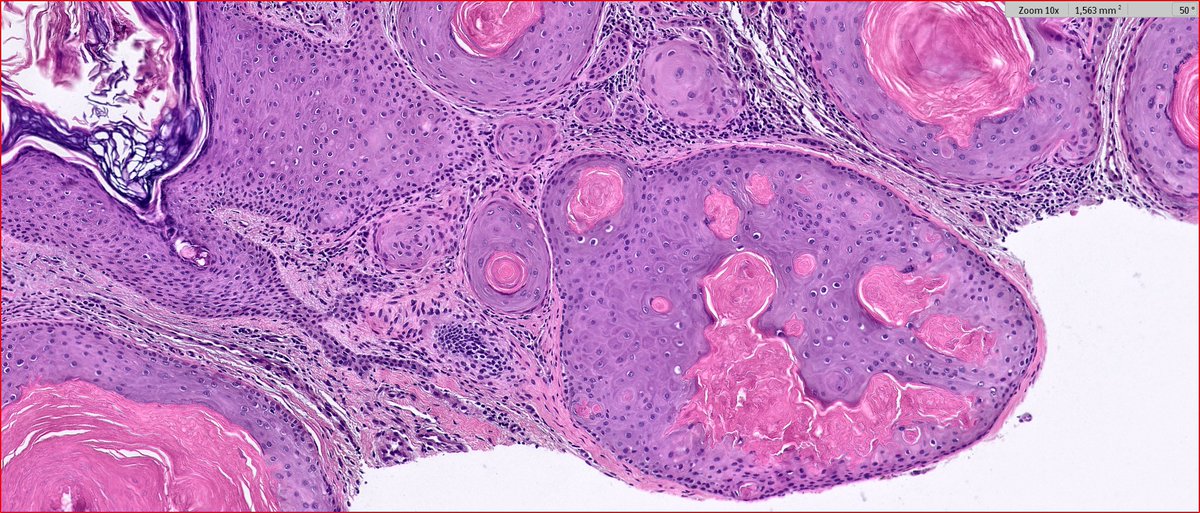

2024 Wk46 ish! RAC9183. M80s Right temple lesion. Previous skin cancers. #TooFarToDiagnose ? #Dermpath

While keratoacanthoma (KA) has historically been considered a variant of cutaneous squamous cell carcinoma (cSCC), current evidence suggests that they are distinct lesions.

What are the differences between KA and cSCC? Find out more in this review: ow.ly/pciN50FccGs